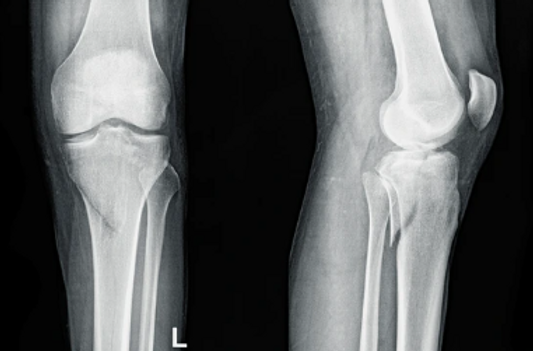

骨が完全に折れず、「ヒビ」が入っている状況を不全骨折といいます。この場合、レントゲンでも写らない事があるため、MRI・CTなどの精密検査を行わなければ正確な診断ができない場合があります。しかし、場所によってはは捻挫と同じ症状となることがありますが、自己判断のみは禁物です。状況によっては、骨が崩れてしまうことがあるので、必ずお怪我の際の状況をご説明ください。